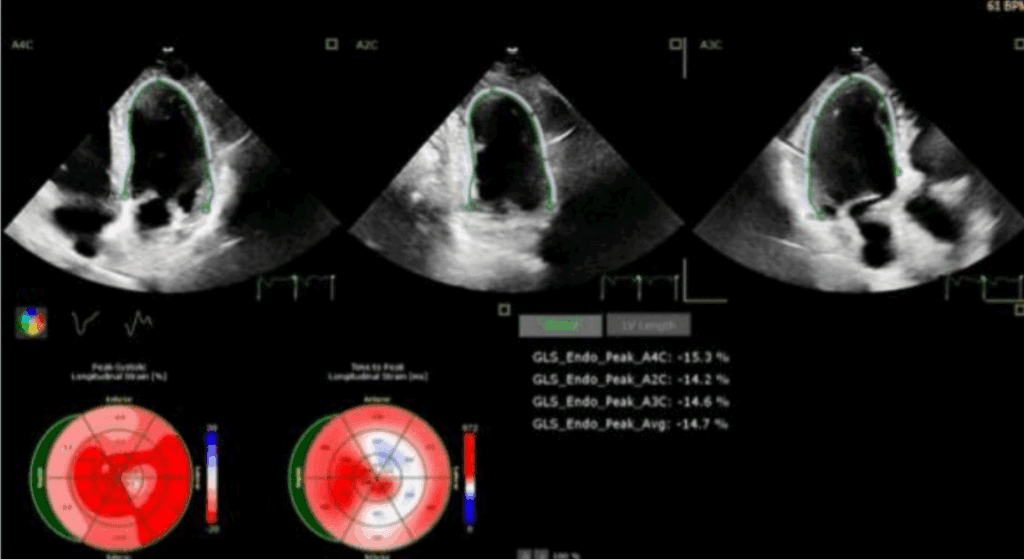

Odkształcenie mięśnia sercowego (strain) jest metodą szeroko wykorzystywaną w diagnostyce echokardiograficznej w grupie chorych z przerostem mięśnia lewej komory serca (ang. left ventricular – LV) o różnej etiologii. W tej grupie chorych standardowe przezklatkowe badanie echokardiograficzne (ang. transthoracic echocardiography – TTE) rozszerzone o pomiar odkształcenia lewej komory serca (ang. left ventricular strain – LV-GLS) ułatwia rozpoznanie, jak i pozwala na różnicowanie przyczyn przerostu LV.

W artykule przedstawiono przypadki kliniczne różnych pacjentów z chorobami układu sercowo-naczyniowego oraz przerostem mięśnia sercowego, u których pomiar odkształcenia (strain) LV istotnie ułatwia diagnostykę różnicową.